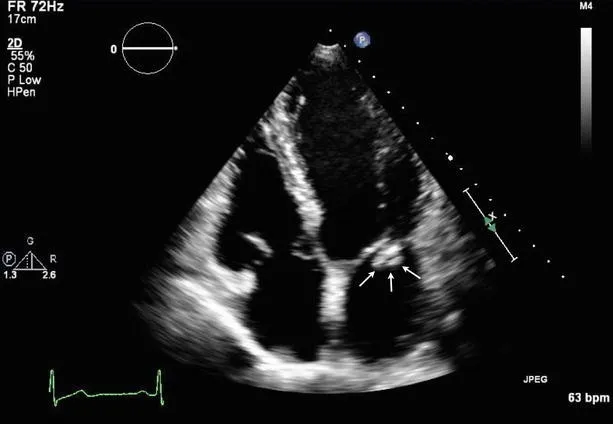

- Echocardiogram (TTE/TEE) to detect vegetations on heart valves.